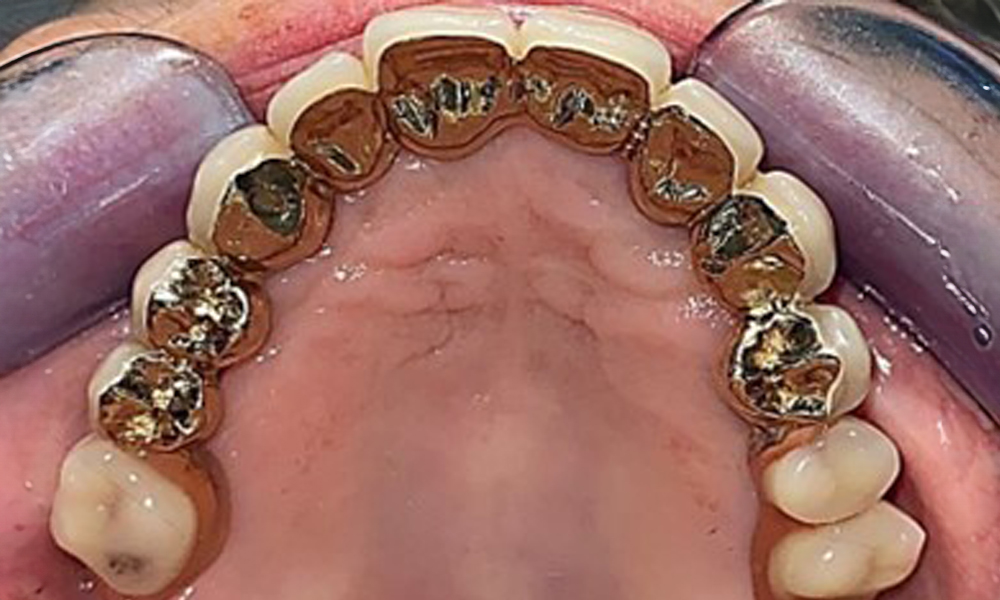

Die Patientin wurde vor über 25 Jahren mit einer kombinierten herausnehmbare Implantat-Teleskopprothese im Oberkiefer versorgt (Abb. 1, Abb. 2, Abb. 3) und ist sehr glücklich über ihren Zahnersatz. Im Unterkiefer hat die Patientin einen suffizienten festsitzenden Zahnersatz. (Abb. 4)

Okklusalansicht: Oberkiefer mit Zahn- und implantatgetragenen Teleskopen.

Abb. 2: Okklusalansicht: Oberkiefer mit Zahn- und implantatgetragenen Teleskopen.